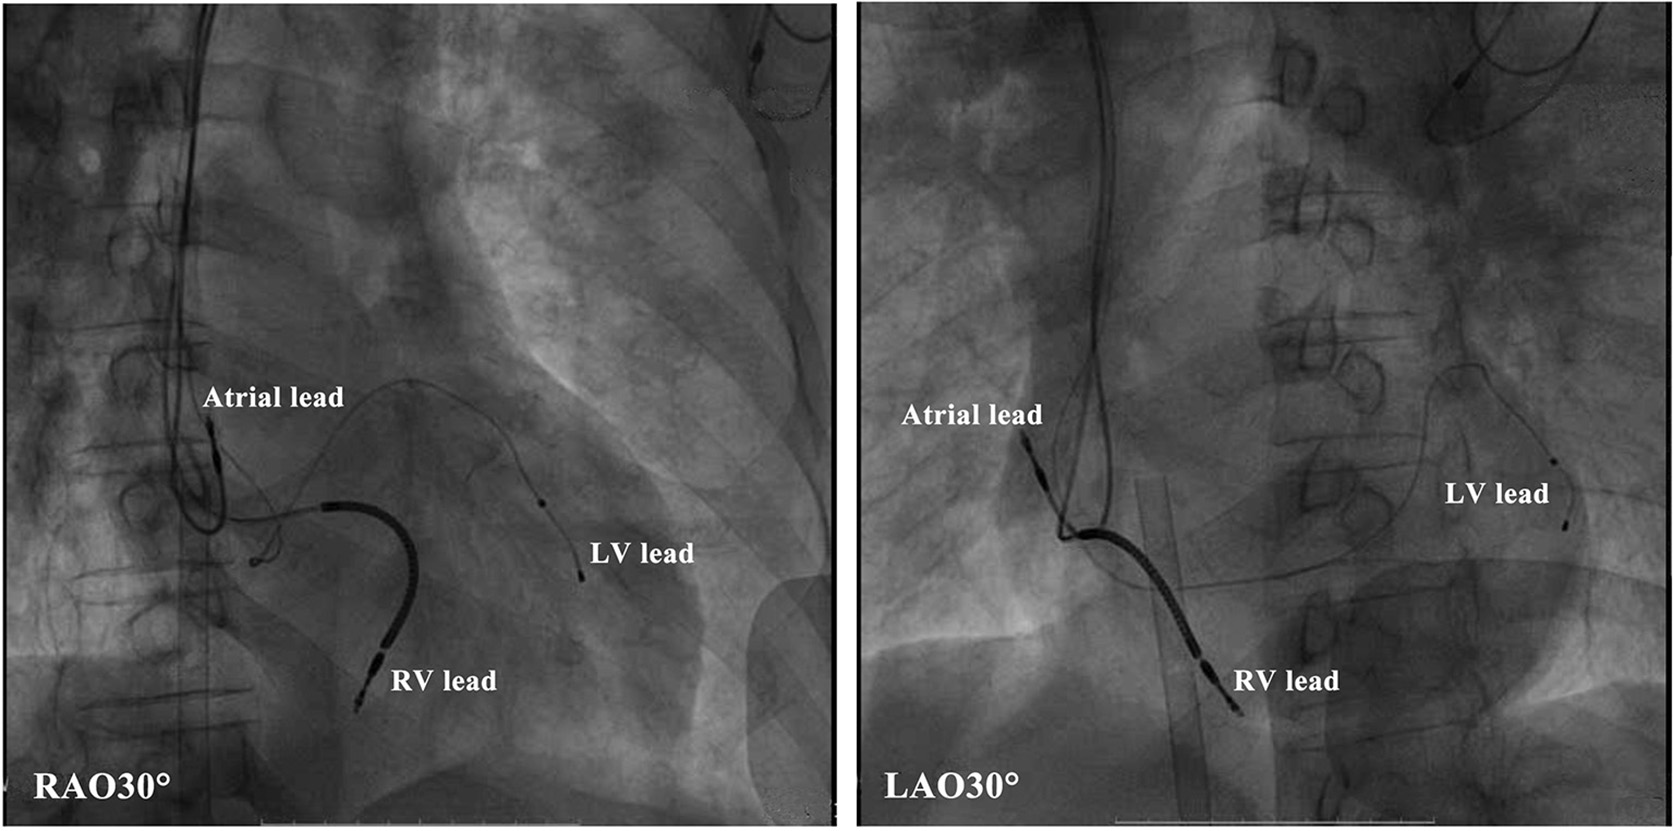

Figure 4

Radiologic images of the cardiac resynchronization therapy system showing lead positioning. LV, left ventricular; RV, right ventricular.

This evaluation led to the recommendation of an upgrade to cardiac resynchronization therapy with defibrillation (CRT-D). Due to the deterioration of heart function, even after appropriate heart failure therapy, the patient consented to the upgrade. The procedure was successfully performed with extracorporeal membrane oxygenation support (Figure 4). The intracardiac recordings from the right and left ventricle showed marked intraventricular conduction delay (200 ms) (Figure 3B). When the ECG was recorded simultaneously with intracardiac recording, we found that the first QRS complex in surface ECG was the result of depolarization of the right ventricle and the second QRS complex was due to depolarization of the left ventricle. Following postimplant ECG optimization, the interventricular interval was narrowed from 200 ms in intrinsic intraventricular conduction to 20 ms in biventricular pacing (Figures 3B,C). After turning on CRT-D, the fused E/A waves were separated in TTE, which suggested that the heart responded well to the CRT-D therapy (Figure 5). As a result, the symptoms of the patient improved significantly. The width of the intrinsic QRS complex was not recovered during an 18-month follow-up. The detailed timeline of the clinical course of this patient is displayed in Table 1.